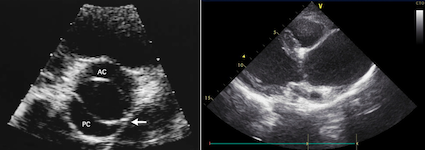

Visitiamo un ragazzo di 12 anni, giunto alla nostra attenzione per un soffio cardiaco auscultato alla visita medico-sportiva. In anamnesi lamenta cefalea. La pressione arteriosa agli arti superiori è di 140/95 mmHg, superiore alla norma per età e altezza, e il gradiente rispetto agli arti inferiori nella misurazione pressoria ai 4 arti è superiore ai 20 mmHg; si apprezza un soffio sistolico rude irradiato al dorso. Nelle sedi femorali e tibiali si palpano polsi apparentemente deboli, i polsi brachiali e radiali sono invece ben presenti. L’ecocardiografia mostra una valvola aortica bicuspide displasica e una dilatazione abnorme a monte della coartazione con flusso turbolento al colorDoppler (Figura 1). Si indirizza il ragazzo alla correzione (angioplastica e stent della coartazione, successiva sostituzione dell’aorta ascendente), con graduale normalizzazione dei valori pressori.